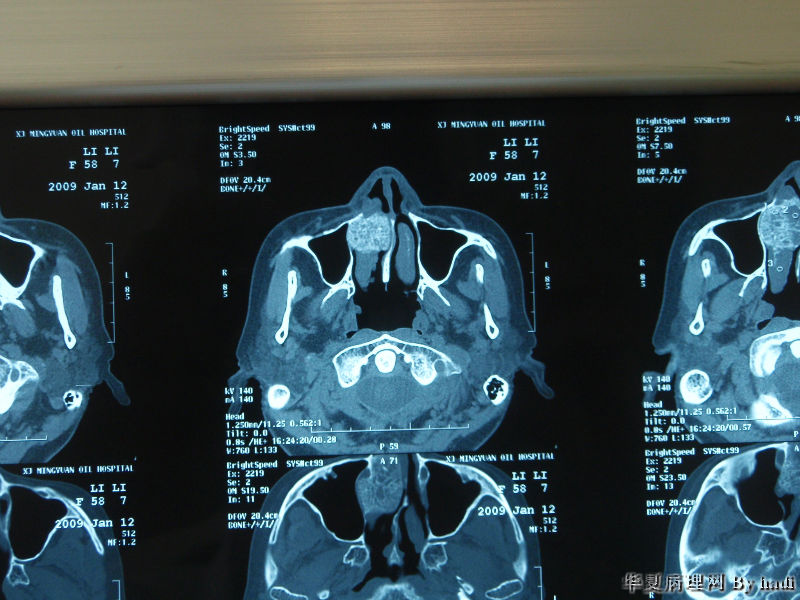

鼻腔肿瘤

鼻腔肿瘤,成人男性

图1

图2

图3

图4

图5

图6

图7

图8